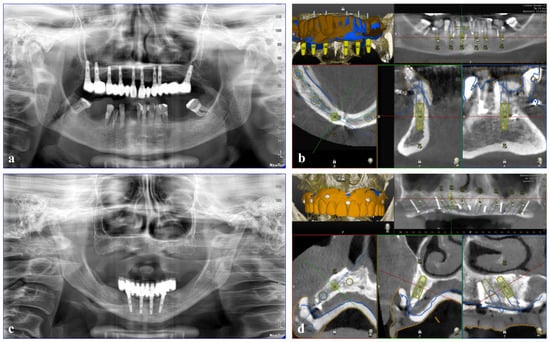

2.3.1. Plan

CBCT images (NewTom Giano HR, Cefla, Imola, Italy, with a field of view of 11 × 5 cm2 and a resolution of 300 µm) in Digital Imaging and Communications in Medicine (DICOM) format, along with stereolithography (STL) files from an intraoral surface scanner (Primescan, Dentsply Sirona, Charlotte, NC, USA), were obtained from each patient. Subsequently, these images were imported into Navident software (ClaroNav Inc., Toronto, ON, Canada) and semi-automatically overlapped onto an ideal digital wax-up of the missing teeth, which was created and tested on the patient according to functional and aesthetic criteria. For this purpose, five to six mini-screws (Ustomed Instruments Ulrich Storz GmbH & Co., KG, Tuttlingen, Germany) were placed on the wax and the hard tissue structures of the affected arch, allowing for comprehensive visualization of the case (both through CBCT and STL images) and serving as landmarks for prosthetic planning of the implant placement, followed by tracing the patient’s teeth (Figure 1).

Figure 1. Implant planning for dynamic computer-aided implant surgery (dCAIS) in the (a,b) mandible and (c,d) maxilla. (a,c) Cone-beam computed tomography (CBCT) images of the initial situation. (b,d) Stereolithography (STL) images overlapped with the digital wax-up incorporating landmarks.